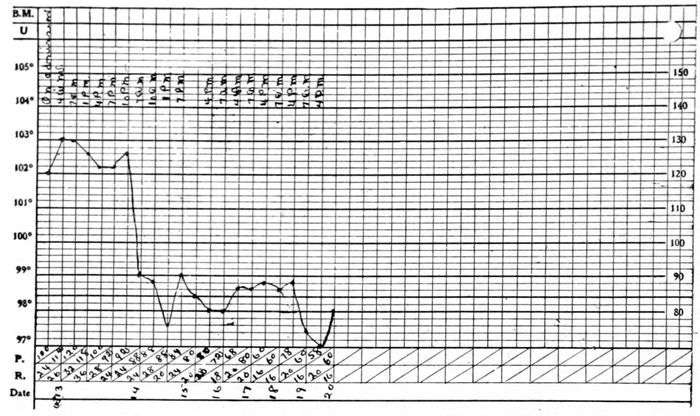

In all descriptions of the disease the duration is spoken of as “several days, more or less,” “a three-day fever,” or “a seven-day fever.” Because of the careful supervision under which the soldiers were kept while in the barracks an excellent opportunity was afforded to note the duration of uncomplicated cases. The shortest time observed was 1 day, and the longest 10 days. The average duration of temperature among 87 soldiers without inflammation of the lungs or other certain complications was 6⅓ days. Among the civilians the shortest time of pyrexia was a few hours only, while the longest in 73 male patients was 14 days, and in 84 female patients was 16 days. The average length of pyrexia in the males was 4⅝ days, and in the females was 5¼ days.